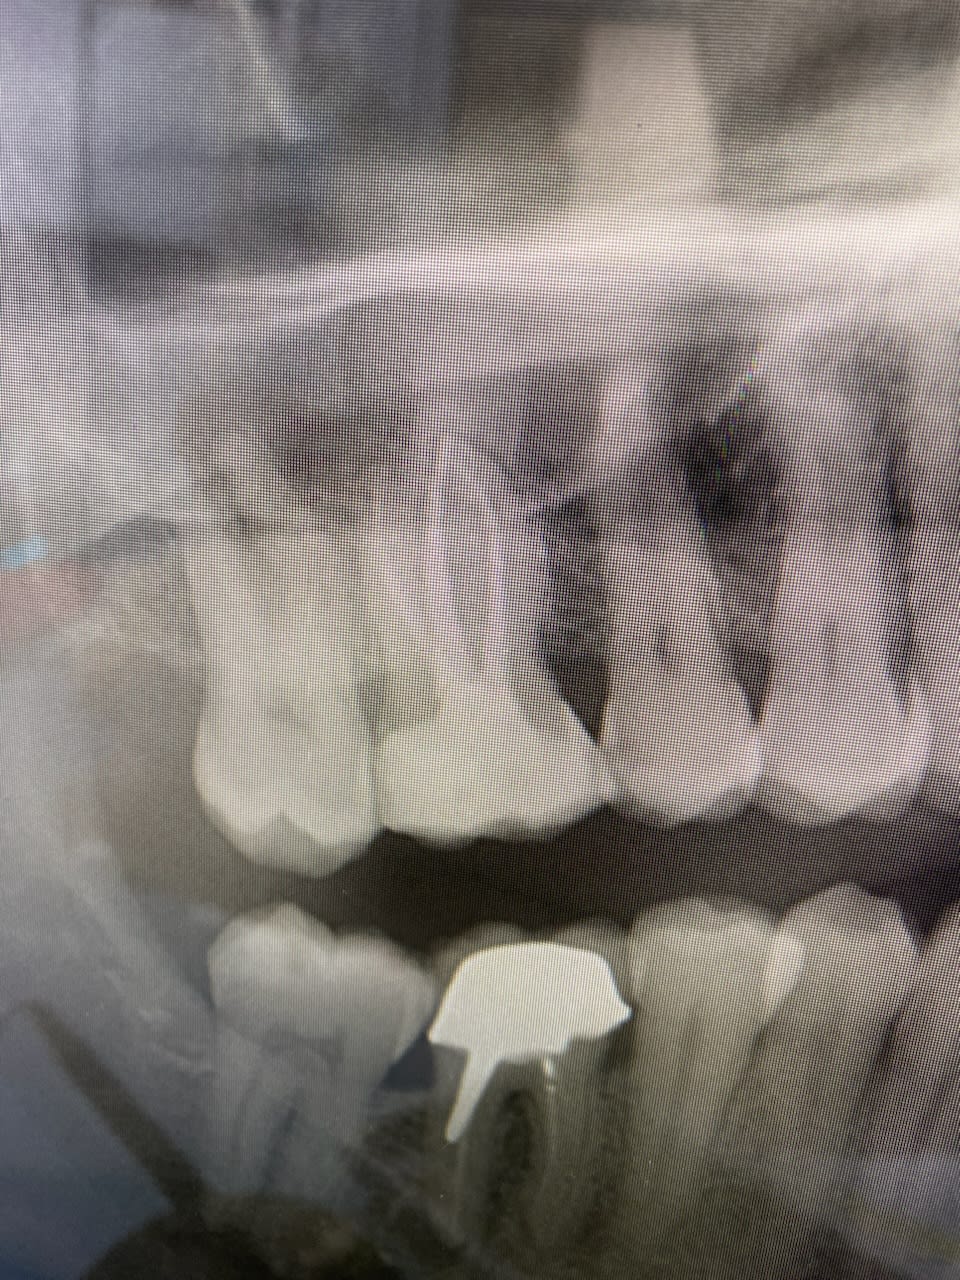

J’ai eu un patient en consultation, il se présente car l’ORL a vu un petit épaississement de la paroi sinusienne.

En lisant le scan et le compte rendu je vois que c’est au niveau de la 16 déjà dévitalisée le traitement a l’air bon.

À la radio il y a une masse radio-opaque. Aucun symptôme de la part du patient.

Oui j’ai fait une retro que je n’ai pas prise en photo mais on voyait à peu près la même chose : une masse radio-opaque au niveau des apex.